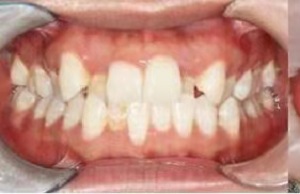

我的牙齿看起来乱七八糟的,简直就像是獠牙,因此想要通过鄞州儿童口腔医院的帮助下,让我的牙齿得到纠正,变成整齐的牙齿。

术前图片

牙齿纠正手术除了牙齿感觉到一点麻以外,倒是没什么了,最后也是顺利地完成,医生进行了后期恢复事宜的讲解。

术后图片

做完之后,牙齿明显得到了好装,真的是一幅整齐的牙齿了,感谢鄞州儿童口腔医院的帮助。